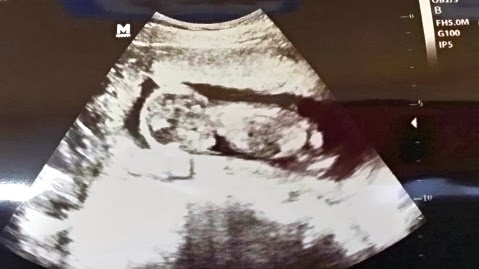

I had my 14 week checkup this week. Everything is looking good. I measured at 15 weeks. The babies heart rate was 160. Could this mean it is a girl? I still have no real feeling if it is a boy or a girl, unlike with Zuri, I knew she was a girl. Zuri's heart rate at her 14 week appointment was 163. I am actually weighing the same this pregnancy as last pregnancy, despite looking much bigger. I asked the nurse if we could have another ultrasound picture, just for fun and she said she didn't have another patient after me for awhile so we could! Yay! The baby is so much bigger in 4 weeks! We didn't do any measurements or anything, just a fun picture. However, the baby is definitely camera shy. We still haven't gotten a great picture, but this one is pretty good. The legs are "frogged" up. Space is looking pretty slim in there!